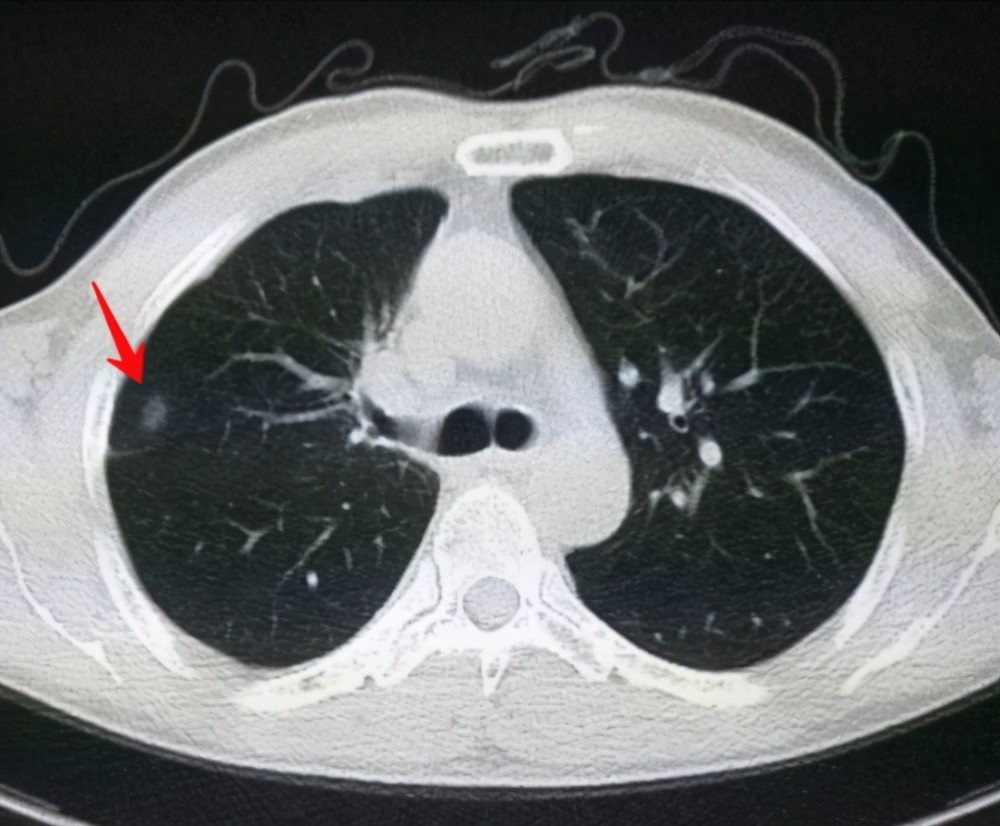

6、定期體檢:定期進(jìn)行肺部檢查,及時發(fā)現(xiàn)并治療肺結(jié)節(jié)。